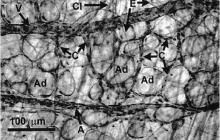

지방흡입의 포인트는 흡입된 지방이 아니라 남겨진 지방이다.

지방흡입의 포인트는 흡입된 지방이 아니라 남겨진 지방이다. 지방흡입 수술은 서구나 남미에서는 이미 전체 미용성형 수술중 가장 많은 부분을 차지하고 있으며, 근래에는 우리나라에서도 얼굴의 성형에서 차츰 체형성형에 관심이 많이 증가 하고 있습니다. ...